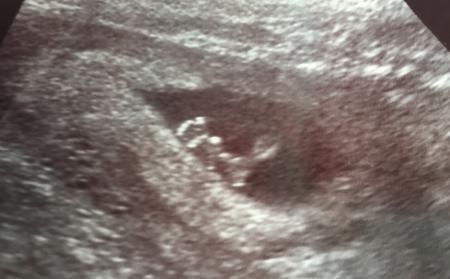

Hallo Wir hatten heute das Screening und alles sah gut aus, ist ein ziemlicher Windfang und hat nur rumgeturnt Lg Monique

Bild zu First Trimester Screening - Forum für August - Mamis

Und echt schöne Bilder! Man kann so richtig gut das Gesicht erkennen.

das sind ja sooooo geniale Bilder! Alles Gute für Euch!!! LG BELLA